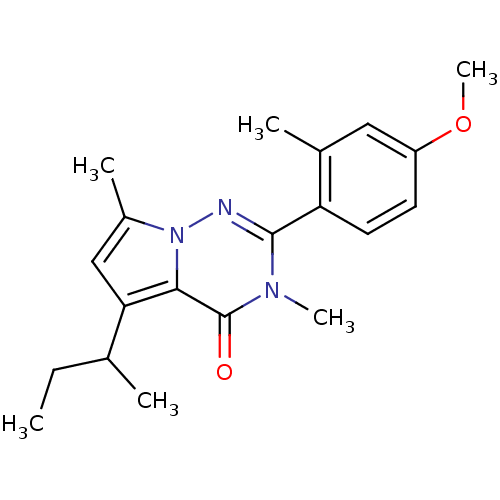

TargetCorticotropin-releasing factor receptor 1(Homo sapiens (Human))

Dupont Pharmaceuticals

Curated by ChEMBL

Dupont Pharmaceuticals

Curated by ChEMBL

Affinity DataEC50: 0.300nMAssay Description:Antagonist activity at human CRF1 receptor expressed in CHO-K1 cells assessed as CRF-stimulated cAMP accumulation by enzyme immunoassayMore data for this Ligand-Target Pair

Affinity DataEC50: 0.420nMAssay Description:Antagonist activity at CRF-R1 in mouse AtT-20 cells assessed as inhibition of human CRF induced cAMP accumulation after 30 mins by radioimmunoassayMore data for this Ligand-Target Pair

Affinity DataEC50: 0.440nMAssay Description:Antagonist activity at CRF-R1 in mouse AtT-20 cells assessed as inhibition of human CRF induced cAMP accumulation after 30 mins by radioimmunoassayMore data for this Ligand-Target Pair

Affinity DataEC50: 0.450nMAssay Description:Antagonist activity at CRF-R1 in mouse AtT-20 cells assessed as inhibition of human CRF induced cAMP accumulation after 30 mins by radioimmunoassayMore data for this Ligand-Target Pair